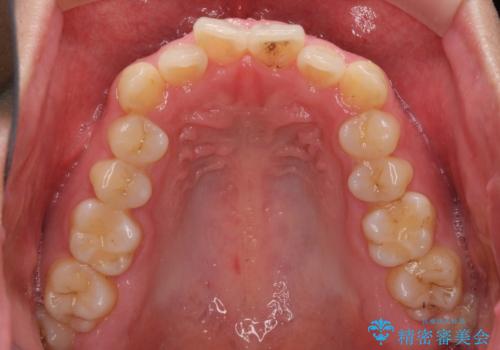

狭い歯列と前歯のデコボコ インビザラインによる矯正治療

- 上下前歯のデコボコを気にして来院された患者様です。

インビザラインによる上下歯列の拡大と、IPR(歯と歯の間を削る)にるスペースの獲得により、前歯のデコボコと狭い歯列を改善することとしました。

比較的軽度な歯列不正であったため、治療期間はそれほど長くはならないと予想されました。

しかしながら、あまりしっかりとマウスピースを装着していなかったため、思いの外期間が長引いてしまいました。

また、仕上がりの歯列にも若干の叢生が残ってしまいました。